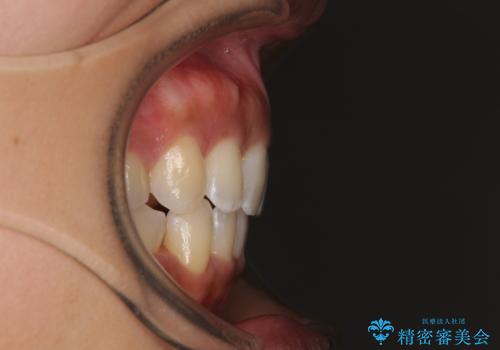

- 下唇が突き出るような口元の突出感が気になるとのことで来院された患者様です。

上下顎ともに前突した歯列であったので、上下ともに左右の第1小臼歯4本を抜歯し、ワイヤー装置にて矯正治療を行うこととしました。